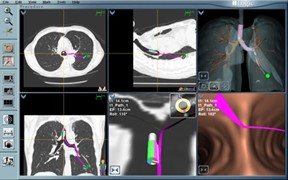

Sammenlignet med konventionel fluoroskopi kan højopløselig 3D-billeddannende CT-konstruktion i forbindelse med en bronkoskopi give real time CT-billeder, således at bronkoskopet eller biopsiværktøjer kan guides direkte til læsionen, som kan biopteres under direkte vejledning af CT.

I de senere år har CBCT med integreret augmented fluoroskopi vist sig at være en lovende billeddiagnostisk modalitet til lokalisation og bioptering af perifere lungelæsioner ved bronkoskopi. CBCT kan både benyttes i kombination med navigationsbaserede robotsystemer eller som ”stand alone” system sammen med det konventionelle bronkoskop (herunder de ultratynde bronkoskoper). CBCT tillader 3-dimensionel billeddannelse og mulighed for segmentation af luftvejene ud til infiltratet i planlægningsfasen, real time augmented fluoroskopi under selve proceduren samt bekræftelse af placering af skop og biopsiværktøjer i læsionen i forbindelse med biopteringen (tool in lesion).

Billede 3: CBCT med augmented fluoroskopi